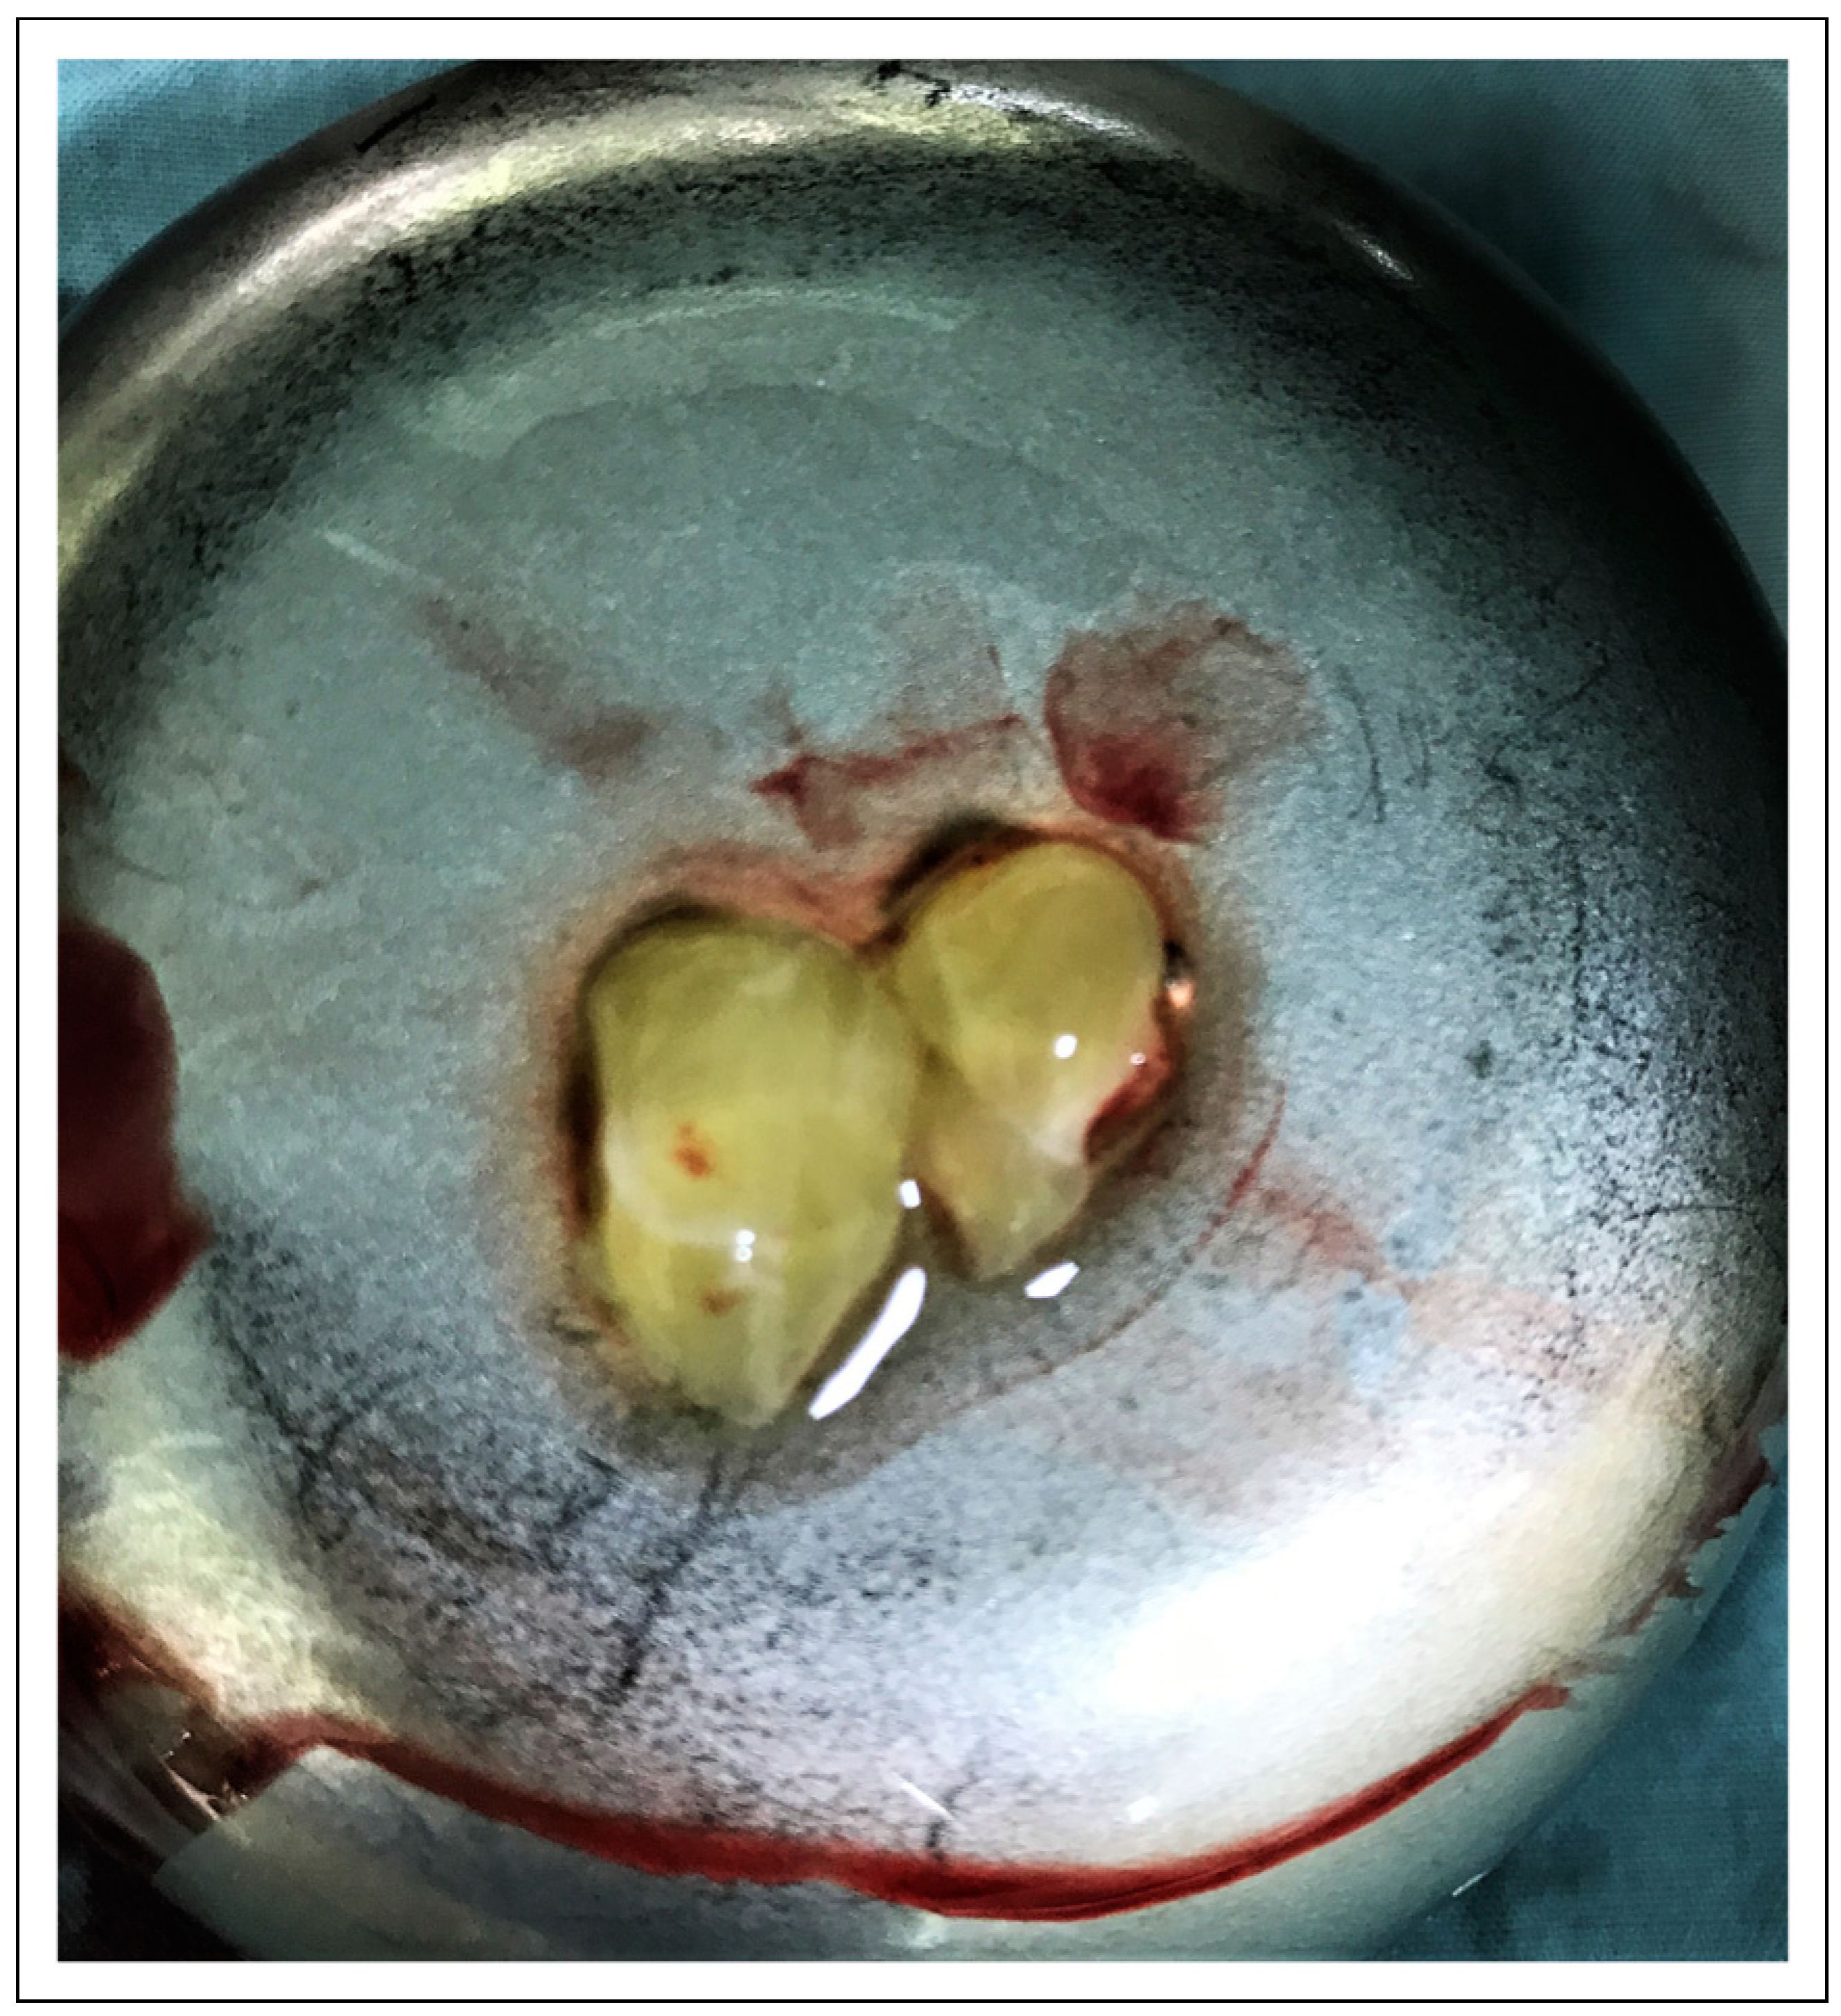

Preparation of the PRF